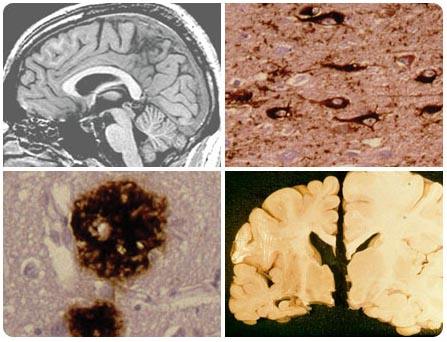

阿尔茨海默病(Alzheimer’s disease,AD)又称老年性痴呆,本病由德国Alois Alzheimer首先描述,它是一种与年龄相关的神经系统变性病,病理以神经炎性斑(neuritic plaques,NP)、神经原纤维缠结(neurofibrillary tangles,NFT)、神经元死亡为特征。临床主要表现为记忆障碍、认知障碍、人格改变等,严重影响患者的生活和社交能力。其发病机制尚未完全阐明,现就其主要学说作一探讨。

正常大脑                                          阿斯海默症萎缩的大脑